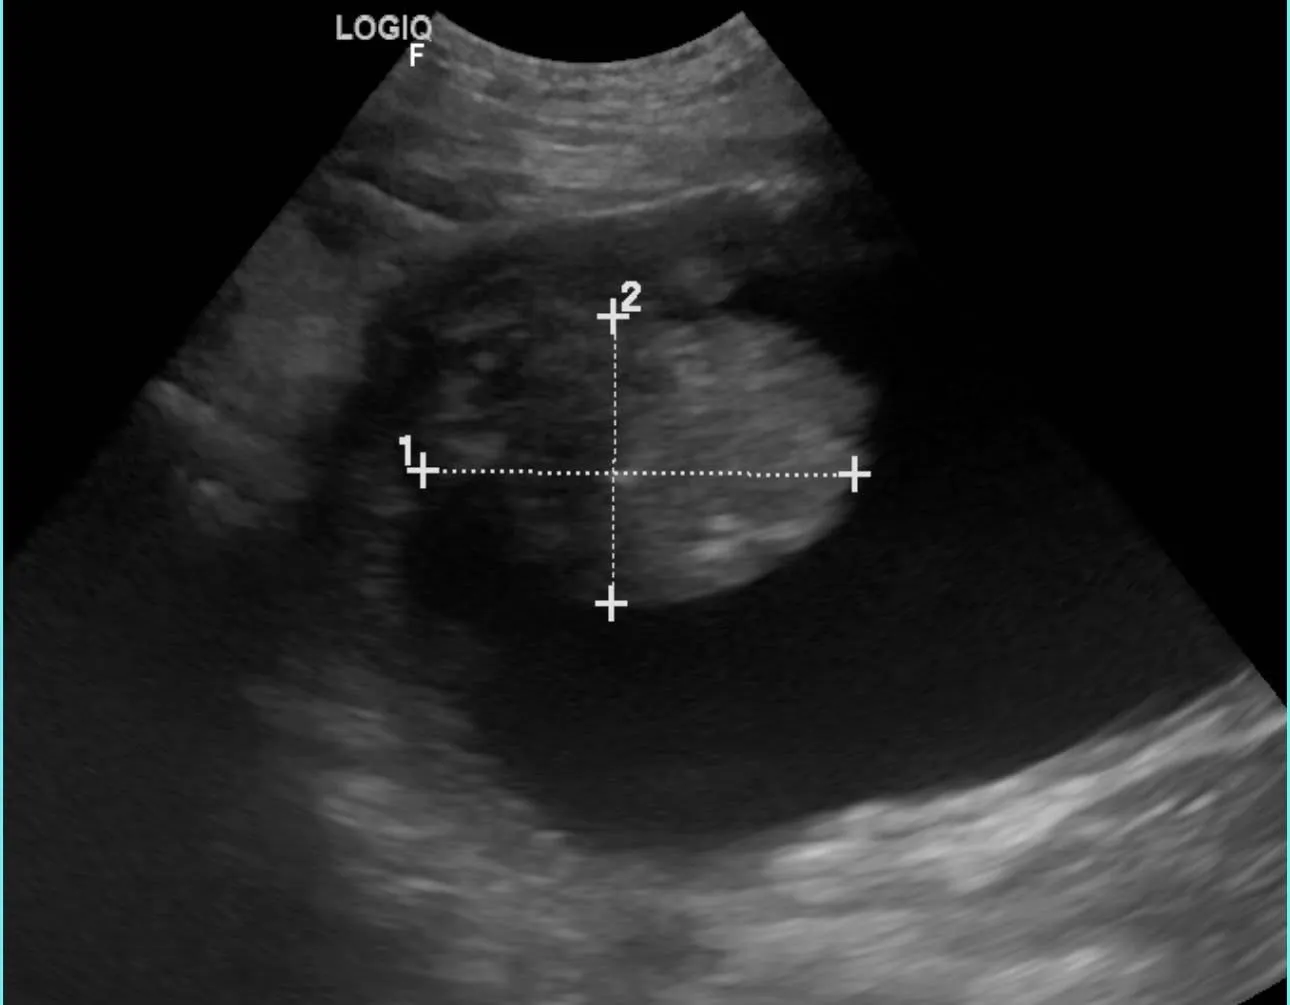

「血尿、頻尿,都是膀胱炎、感染嗎? 小心隱形殺手膀胱癌!」—犬膀胱癌須知

2026/04/15我們最常聽到的一句話是:

「醫師,他已經尿尿怪怪很久了,一直蹲廁所,亂尿尿,血尿,在其他醫院開抗生素,也沒有比較好。」

遇到這樣的情況,我們大約有警覺事情可能沒這麼單純:

但有些案例,背後真正的原因是腫瘤——

犬膀胱移行上皮癌(Transitional Cell Carcinoma,TCC) -